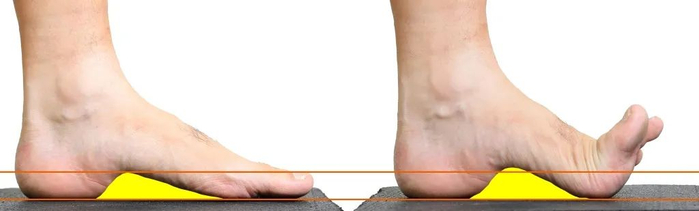

现代跑鞋鞋头都是上翘的,为什么要设计成上翘的鞋头,据称这样的设计有利于快速滚动着地,缩短触地时间,提高跑步效率。

但这样的设计也会带来由于大脚趾的轻度上翘,会引发足底筋膜的卷扬机效应,导致筋膜处于缩短紧张状态,张力增加。

结果发现,由于鞋头跷度的存在,导致在脚趾离地过程中,跖趾关节主动背屈角度变小,但并没有因此减少足底刚度,也就意味着在更小的脚趾活动中,足底筋膜产生了更大的张力;

同时这种更大张力产生本身也跟鞋头跷度导致的静止状态下,足底筋膜本身就存在一定张力,并随着跖趾关节背屈,张力进一步累加有关。

也就是说由于鞋头跷度的存在,增加了足底筋膜的张力,有利于减少跖趾关节处的力矩,也即足底筋膜可能会减轻足底肌肉的活动。

换句话说,鞋头上翘能让连接足趾与足骨关节周围的肌肉减少做功,让跑步更省力,但这样做的代价就是足底筋膜张力增加。